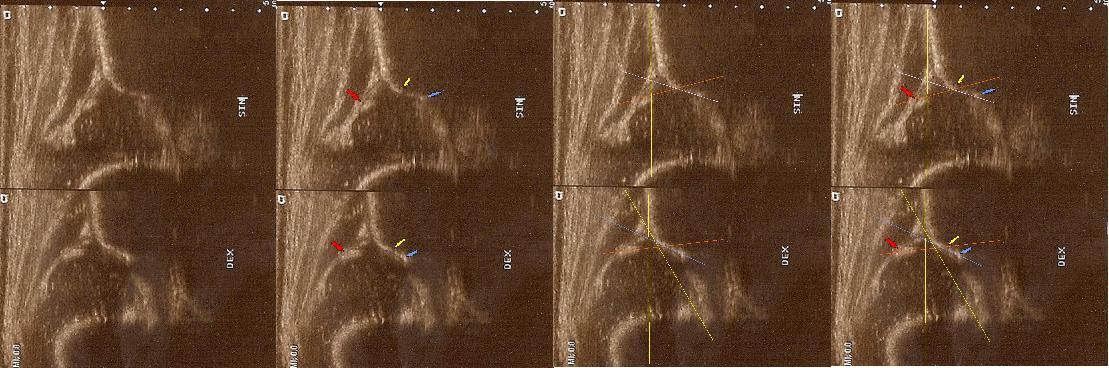

typIIa 6tyg.ż. dach kostny wystarczajacy;brzeg kostny kanciasty(mimo dysplastycznej panewki) pierwsza część dachu dobra ,

druga głębsza stroma(trzeba na to uważać) ;dach chrzestny pokrywa

górne zdjęcia strzałki pokazują obrabek(czerwona):brzeg kostny (żółta);gałąż dolna(niebieska) ,

prawidłowy przebieg linii dachu kostnego(niebieska) stycznie do echa gałęzie dolnej i echa brzegu kostnego ;

linii dachu chrzęstnego (czerwona) stycznie do brzegu kostnego i przez środek geometryczny obrąbka i

linii podstawnej ( żółtarównolegle do sylwetki kości biodrowej po zewnetrznej stronie prze punkt gdzie ochrzęstne przechodzi w okostna i styka sie z echem kości

dolny staw prawidłowy Typ I dach kostny dobry;brzeg kostny tępy ;dach chrzestny pokrywa

dolne zdjęcia strzałki pokazują obrabek(czerwona):brzeg kostny (żółta);gałąż dolna(niebieska) ,

linii podstawnej ( żółta

typIIa 4yg.ż. dach kostny wystarczajacy;brzeg kostny okragły;dach chrzestny pokrywa

linii podstawnej ( żółta)równolegle do sylwetki kości biodrowej po zewnetrznej stronie

przez punkt gdzie ochrzęstne przechodzi w okostna i styka sie z echem kości

typ II/ D powyżej 4tyg.ż. dach kostny bardzo niewystarczajacy;brzeg kostny spłaszczony

;dach chrzestny przesunięty dogłowowow ( szczyt głowy jest poniżej szczytu dachu chrzęśtnego)

linii podstawnej ( żółta)równolegle do sylwetki kości biodrowej po zewnetrznej stronie prze punkt gdzie ochrzęstne przechodzi w okostna i styka sie z echem kości : w przypadku wysuwania głowy z panewki nie zawsze jest to już pozycja standardowa; sylwetka kosći biodrowej pochyla sie i powiniśmy kreślic linie zgodnie z odchyleniem w lewo druga żółta liinia kropkowana ( trzeba o tym pamiętac bo z D wykreślimy I prawidłowy kąt @ o wartości 62 st .I jest to najczęstszy błąd; u kikutygodniowych niemowląt kiedy zmiany wtórne nie sa jeszcze wykształcone; o poważnych konsekwencjach zwłaszcza jeśli korzystamy z programów do automatycznego wykreslania kątów )